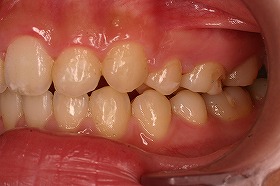

歯の矯正治療 症例ビフォー&アフター

この症例は、出っ歯を矯正治療でキレイにしたケースです。

しっかり噛んでいなかった前歯がかみ合うように並べました。

最初にいらしたときには、出っ歯であることによって

噛み合わせが上手くいかず、口を閉じることが出来ないケースでした。

この場合だと、噛み合わせが悪いだけでなく、

口が常に開いているために、見た目もだらしなくなってしまいます。

さらに、口が開いた状態で生活すると、口の中が乾燥してしまい、

口臭の原因にもなるのです。